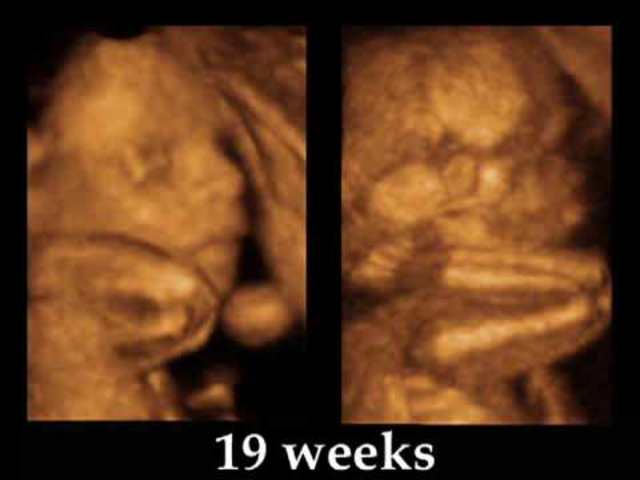

• Week 19

Week 19

At 138 days, you're approximately 19 to 20 weeks. The gender can usually be determined by ultrasound if your baby cooperates. Your baby needs to be sitting in slighty indiscrete positions to catch a tell-tale sign of male or female gender.